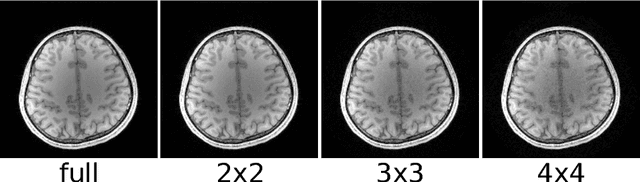

The main disadvantage of Magnetic Resonance Imaging (MRI) are its long scan times and, in consequence, its sensitivity to motion. Exploiting the complementary information from multiple receive coils, parallel imaging is able to recover images from under-sampled k-space data and to accelerate the measurement. Because parallel magnetic resonance imaging can be used to accelerate basically any imaging sequence it has many important applications. Parallel imaging brought a fundamental shift in image reconstruction: Image reconstruction changed from a simple direct Fourier transform to the solution of an ill-conditioned inverse problem. This work gives an overview of image reconstruction from the perspective of inverse problems. After introducing basic concepts such as regularization, discretization, and iterative reconstruction, advanced topics are discussed including algorithms for auto-calibration, the connection to approximation theory, and the combination with compressed sensing.